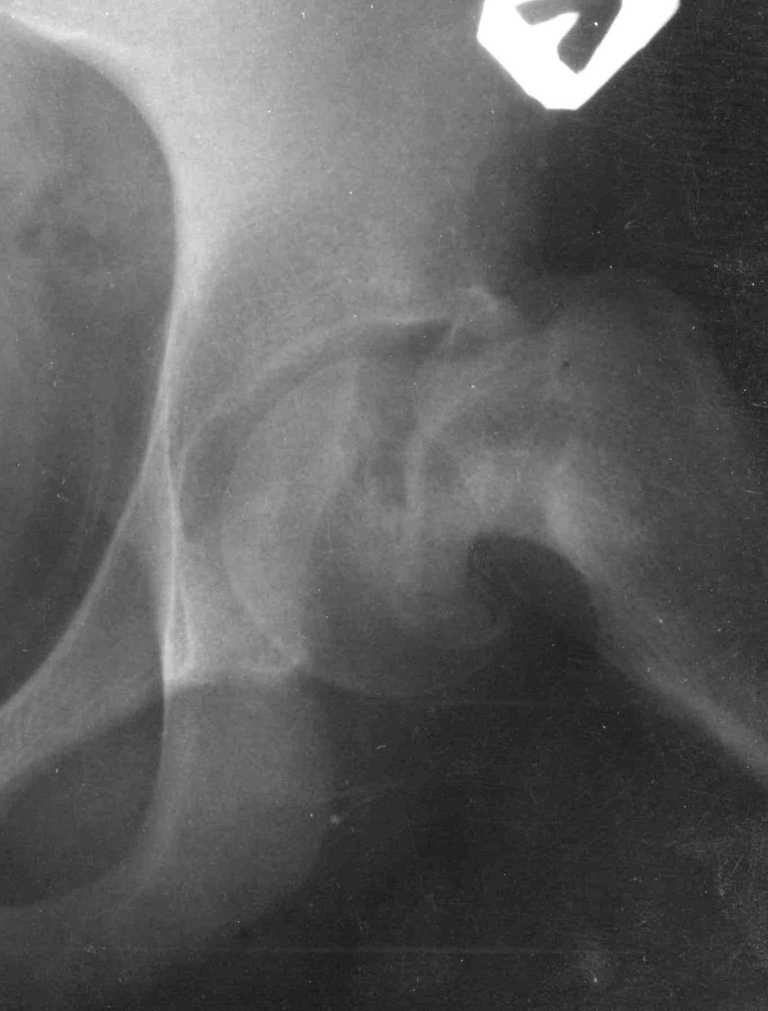

Если стабильность юношеского эпифизиолиза доказана, тогда можно провести коррегирующие операции. Все открытые методы репозиции опасны высоким процентом осложнений из-за повреждения кровоснабжения головки.

Еще Trueta and Harrison, JBJS, 35-B:442, 1953; потом Sevitt and Thompson, JBJS, 47-B:560, 1965 доказали, что медиальная циркумфлекс артерия доставляет от 66-80% крови в головку бедра, поэтому важным является профилактика повреждения медиальной артерии.

Традиционные доступы не всегда гарантируют сохранность сосудов и не создают удобства для реконструктивных работ на шейке.

Группа Reinhold Ganz 1997 году заново изучила топографию кровоснабжения проксимального отдела бедра введением в сосуды жидкого раствора латекса. Результаты диссертации "An anatomical study was carried out at Bern to study the arterial tree of the medial femoral circumflex artery.(Die Arteria circumflexa femoris medialis Topographischer Verlauf, Anastomosen. Inaugral-Dissertation 1997. Ganz, K., Krugel, N)" опубликовали Gautier, E., Ganz K., Krugel N., Gill T., Ganz R.: Anatomy of the medial femoral circumflex artery and its surgical implications. J. Bone and Joint Surg., 82-B(5): 679-683, 2000.

На основе этой работы был предложен анатомичекий доступ к проксимальному отделу бедра, так называемый Digastric или Flip Trochanteric Approach.

Доступ удобен при "circumcision osteoplasty" при импинжменте, при переломах головки, лабральной патологии, при удалении медиальных остеофитов из дна вертлужной впадины, а также при коррекции проксимальной части бедра.

Характерным отличием является то, что Vastus Lateralis and Gluteus Medius остаются прикрепленным к кости. Остеотомия трохантера на уровне прикрепления мышц, потом капсулотомию делают в форме Z вместо Т, что дает лучший обзор. При вывихе головки артерия циркумфлекс защищается сухожилием обтуратора интернус.

Здесь представлен один из случаев остеотомии на шейке после остаточного явления юношеского эпифизиолиза из Flip Trochanteric доступа.